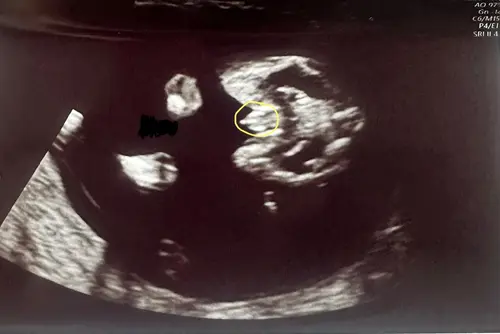

Maar inwendig krengen we dit beeld als eerste te zien, 2 benen met een puntje in het midden.. de verloskundige zei er niks over omdat wij het niet willen weten. Maar nu denk ik dus whaha zou het dan toch echt zo zijn!🤣🙈. We hopen stiekem zelf namelijk als gezin wel op een jongen!🥰

Dit beeld heb ik ook gezien 🤭 mijn gyno zei “we kijken deze echo niet naar het geslacht, ze hebben nu allemaal een verdikking” ja ammehoela 🤣 ik heb al een jongen dus herkende dit beeld direct 😜